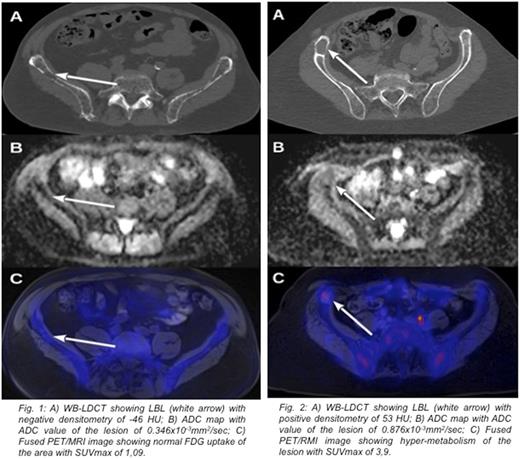

Results: A hundred thirtyfive lytic >5 mm diameter bone lesions were recognized by WB-LDCT in patients under study. Thirtyfive lesions (mean dimension 11,09 SD ± 1,5 mm) had a negative densitometry (mean -57,57 HU; SD ± 33,13 HU) showing high signal in T1w images, low signal in STIR and DWI sequences, while 100 lesions (mean dimension 17,36 SD ± 2,64) presented positive densitometry (mean 44,87 HU; SD ± 23,89) showing low T1w signal and high signal in STIR and DWI sequences. The first group presented low ADC values (mean 0,360x10-3 mm2/sec; SD ± 0,154) and low SUV max values (mean 1,69; SD ± 0,56), while the second group showed higher ADC values (mean 0,868x10-3 mm2/sec; SD ± 0,207) and SUV max values (mean 5,04; SD ± 1,94) (Fig. 1 and Fig.2). Mean ADC values and mean SUV max values between the two groups were statistically different (p value < 0,01). Eight patients presented positive and negative density LBL, 7 patients presented only positive density LBL and 3 patients presented only negative density LBL. In two patients of this latter group who did not start therapy, negative density LBL, became positive in conjunction with biochemical progression disease during the 12 months follow up. In terms of SUV and ADC a significant concordance was found between PET and MRI for both positive and negative densitometry LBL, (91% and 94%, respectively) considering a cut off value of SUV>2 and ADC>0,6 x10-3mm2/sec as abnormal. Finally, we showed a strong statistical correlation between positive densitometry LBL and ADC value >0,8 x10-3 mm2/sec, typical of focal lesion (58% vs. 2,86%, p<0,0001) and between positive densitometry LBL and SUV value >2 (92% vs. 2,86%, p<0,0001).